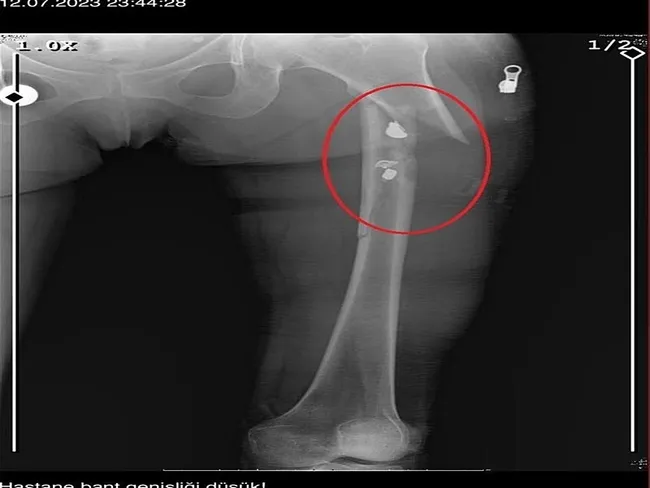

Fatma O., annesine yazdığı mesajda, "Odada ceset var. Telefon dinleniyor. Bana 8 el ateş etti. Yaralıyım. Polisi görürse önce beni öldürecek. Onu parayla kandırıp, evden çıkartın. Sonra da beni alın" dedi. Fatma O.'nun annesi, bu mesaj sonrası polise gidip şikayette bulundu. Polis, Fatma O.'nun annesi aracılığıyla Sarıkaya ile iletişime geçti. Fatma O.'nun annesi, telefonla aradığı Sarıkaya'yı, kızına para götürmesi için evine çağırdı. Ekipler, parayı almaya gelen Sarıkaya'yı kendilerine silah çekmesine rağmen yakaladı. Eve giden ekipler, ağır yaralı haldeki Fatma O. ve kokmaya başlayan cesetle karşılaştı. Emniyetteki işlemlerin ardından Sarıkaya tutuklanıp, hakkında dava açıldı.